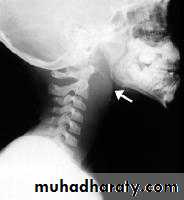

3. Posterior rhinoscopy and fibroptic endoscopy: lobulated mass, which occasionally extends laterally.Investigations

X-ray of the postnasal spaceComplications

Radiography:Plain films like lateral X-Ray of the skull, is needed in nasopharyngeal mass like adenoids, and can demonstrate bone erosion in cases of nasopharyngeal cancer.